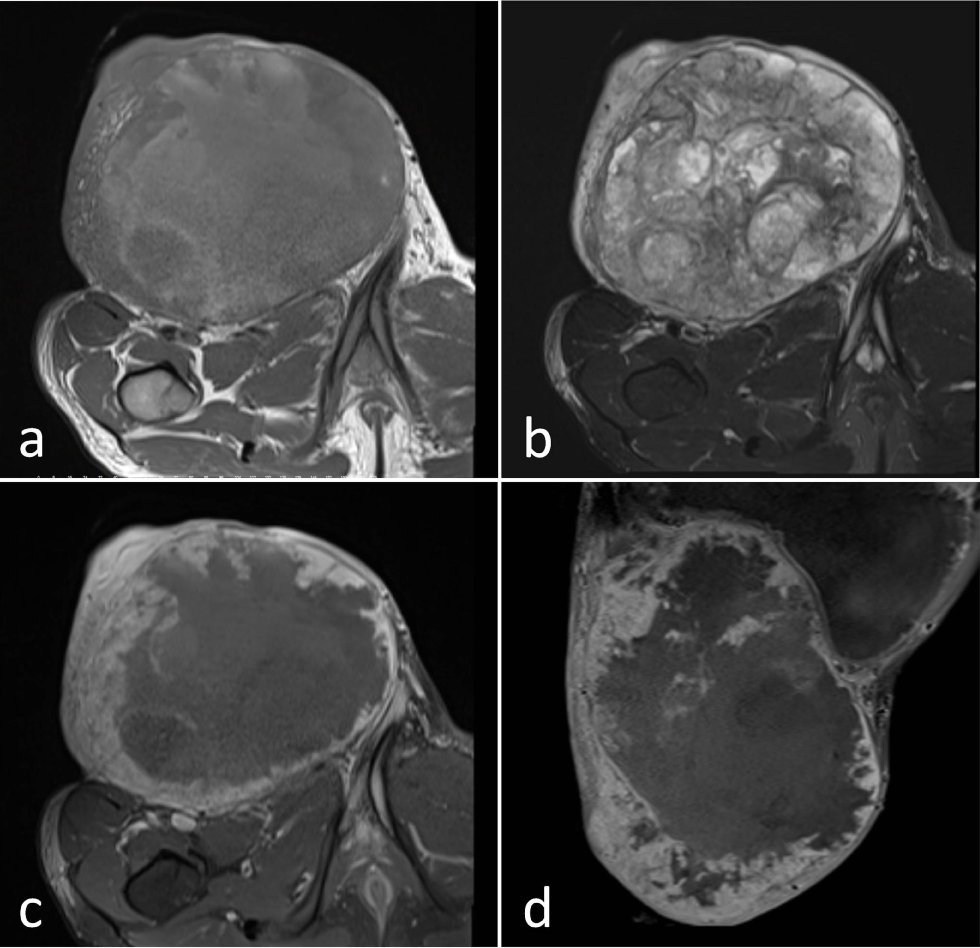

A 19-year-old man was admitted our hospital with right inguinal mass. Ultrasonography (US) showed an irregular, heterogeneous mass lesion in the right ingunal region. Right testis was not seen in scrotum. The patient had no history of any operation. Magnetic resonance imaging (MRI) demonstrated a giant mass which was size of 24 × 17 × 15 centimeter. The mass was hypointense on T1-weighted images, heterogeneous hyperintense on T2-weighted images and heterogeneous contrast enhancement was observed (Figure 1). The lesion was invading the surrounding fat and muscle tissues and also prolonged in the intraabdominal space. The absence of the right testis suggested a testis tumor. Soft tissue sarcoma was considered in differential diagnosis. The lesion was excised and resulted as testicular mixed germ cell tumor (GCT) histopathologically.

Figure 1: MRI shows an irregular, heterogeneous mass lesion in the right ingunal region. The mass is hypointense on T1-weighted images (a), heterogeneous hyperintense on T2-weighted images (b) and after contrast adminstration (c,d) heterogeneous contrast enhancement is observed.